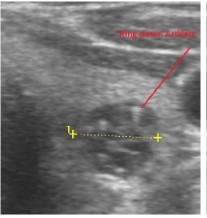

Figure 7.Thyroid nodule suspicious for Parathyroid adenoma due to its location

Despite the fact that nodular pathology was found to be very prevalent among our study population, it has been found difficult to differentiate between thyroid and parathyroid pathology using ultrasound alone. However, some characteristics of the parathyroid glands might suggest parathyroid pathology in the context of the clinical picture of secondary or tertiary hyperparathyroidism which is very prevalent in ESKD patients’ populations.

In our study many patients were found to have nodules look very much like PT adenoma, Figure 7 below. At least, 4 patients were subsequently confirmed to have parathyroid adenomas, Figure 8 and 2 patients underwent surgery